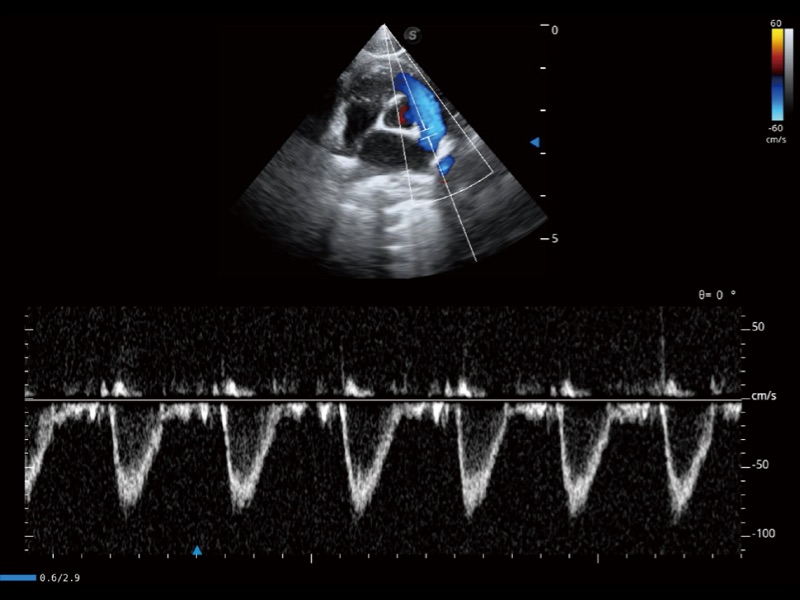

能够基于左心室壁追踪和辛普森法,自动计算射血分数,支持多个可移动点描迹,与手动测量相比,极大节省了动物医生的时间和精力。

通过360度任意调节3条M型取样线,在同一心动周期上观察心脏不同位置的运动曲线,得到准确的心功能测量数据,有效评估心肌运动及左心室功能。

实时用颜色表示心肌组织运动,观察和定量组织的运动情况,对快速检测与评估心肌的灌注和活性、电传导及心肌收缩和舒张功能等均能提供重要的诊断信息。

当心脏测量结果超出正常范围时,可实时预警提示动物医生,减少疾病漏诊概率。